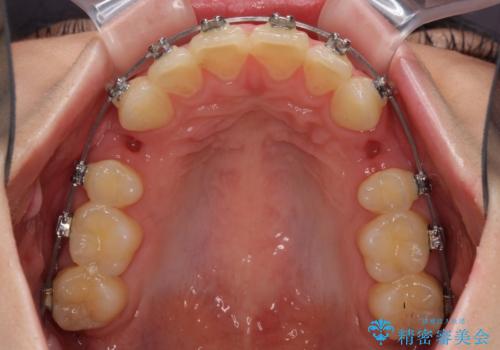

- メタルブラケット

左右ともに上顎奥歯が外を向き、下顎奥歯が内側に倒れているシザーズバイトであったため、補助装置により改善することとしました。

上下の咬み合わせは、下顎に対して上顎が相対的に前方にあったため、奥歯のシザーズバイト改善後に上顎左右第一小臼歯2本を抜歯し、上顎前突を改善していくこととしました。